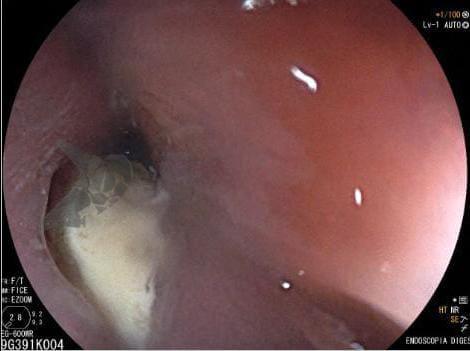

Paciente feminina, 59 anos, portadora de fibrilação atrial paroxística, foi submetida a ablação térmica para tratamento da arritmia. Encontrava-se assintomática até que dez dias após o procedimento iniciou com quadro de dor torácica e sintomas de refluxo. Endoscopia digestiva alta demostrou o seguinte achado: